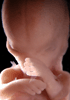

Carnegie Stage 23 (56 post-ovulatory days)

Most embryos at stage 23 are approximately 56-57 postovulatory days old and measure 23-32 mm in length. Distinguishing criteria for this stage include fusion of the eyelids at the medial and lateral margins, clear distinction of the subdivisions of the upper and lower limbs, the forearms appear at or above the level of the shoulders, the superficial vascular plexus of the head is very close to the vertex, and the external genitalia are well developed but not always sufficiently to distinguish the embryo's sex.

(NOTE: These specimens are late stage 23.)